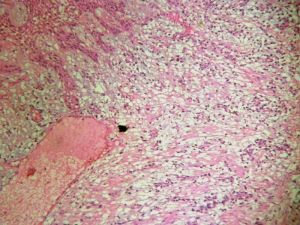

鈣化上皮瘤(calcifying epithelioma),又名毛母質瘤(pilomatrixoma),是由表皮毛皮質分化的細胞腫瘤,含有嗜鹼細胞和影細胞,影細胞來自嗜鹼細胞。新損害中嗜鹼性細胞較多,陳舊損害則較少,甚至不見嗜鹼細胞。病變在真皮深層或皮下,屬皮膚深層良性腫物。